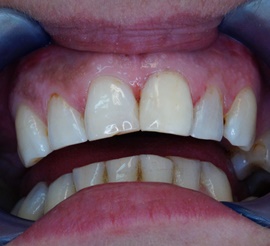

Wybielanie obejmujące pojedyncze zęby jest dość często spotykane. Najczęstszą przyczyną dyskoloracji zęba jest obumarcie miazgi i brak następowego poprawnego leczenia kanałowego, lub leczenie nieprawidłowe. Czasami udaje się przeprowadzić proces wybielania, który jest zadowalający dla pacjenta, a czasami w oparciu o uzyskany wynik można przeprowadzić leczenie protetyczne np. koroną lub licówką całoceramiczną.

Trzeba jednak uważać, ponieważ nieumiejętnie przeprowadzone wybielanie może być przyczyną resorpcji wewnętrznej i może sie skończyć utratą całego zęba...juz wybielonego. Poniżej zdjęcia przed i po leczeniu mikrochirurgicznym resorpcji.